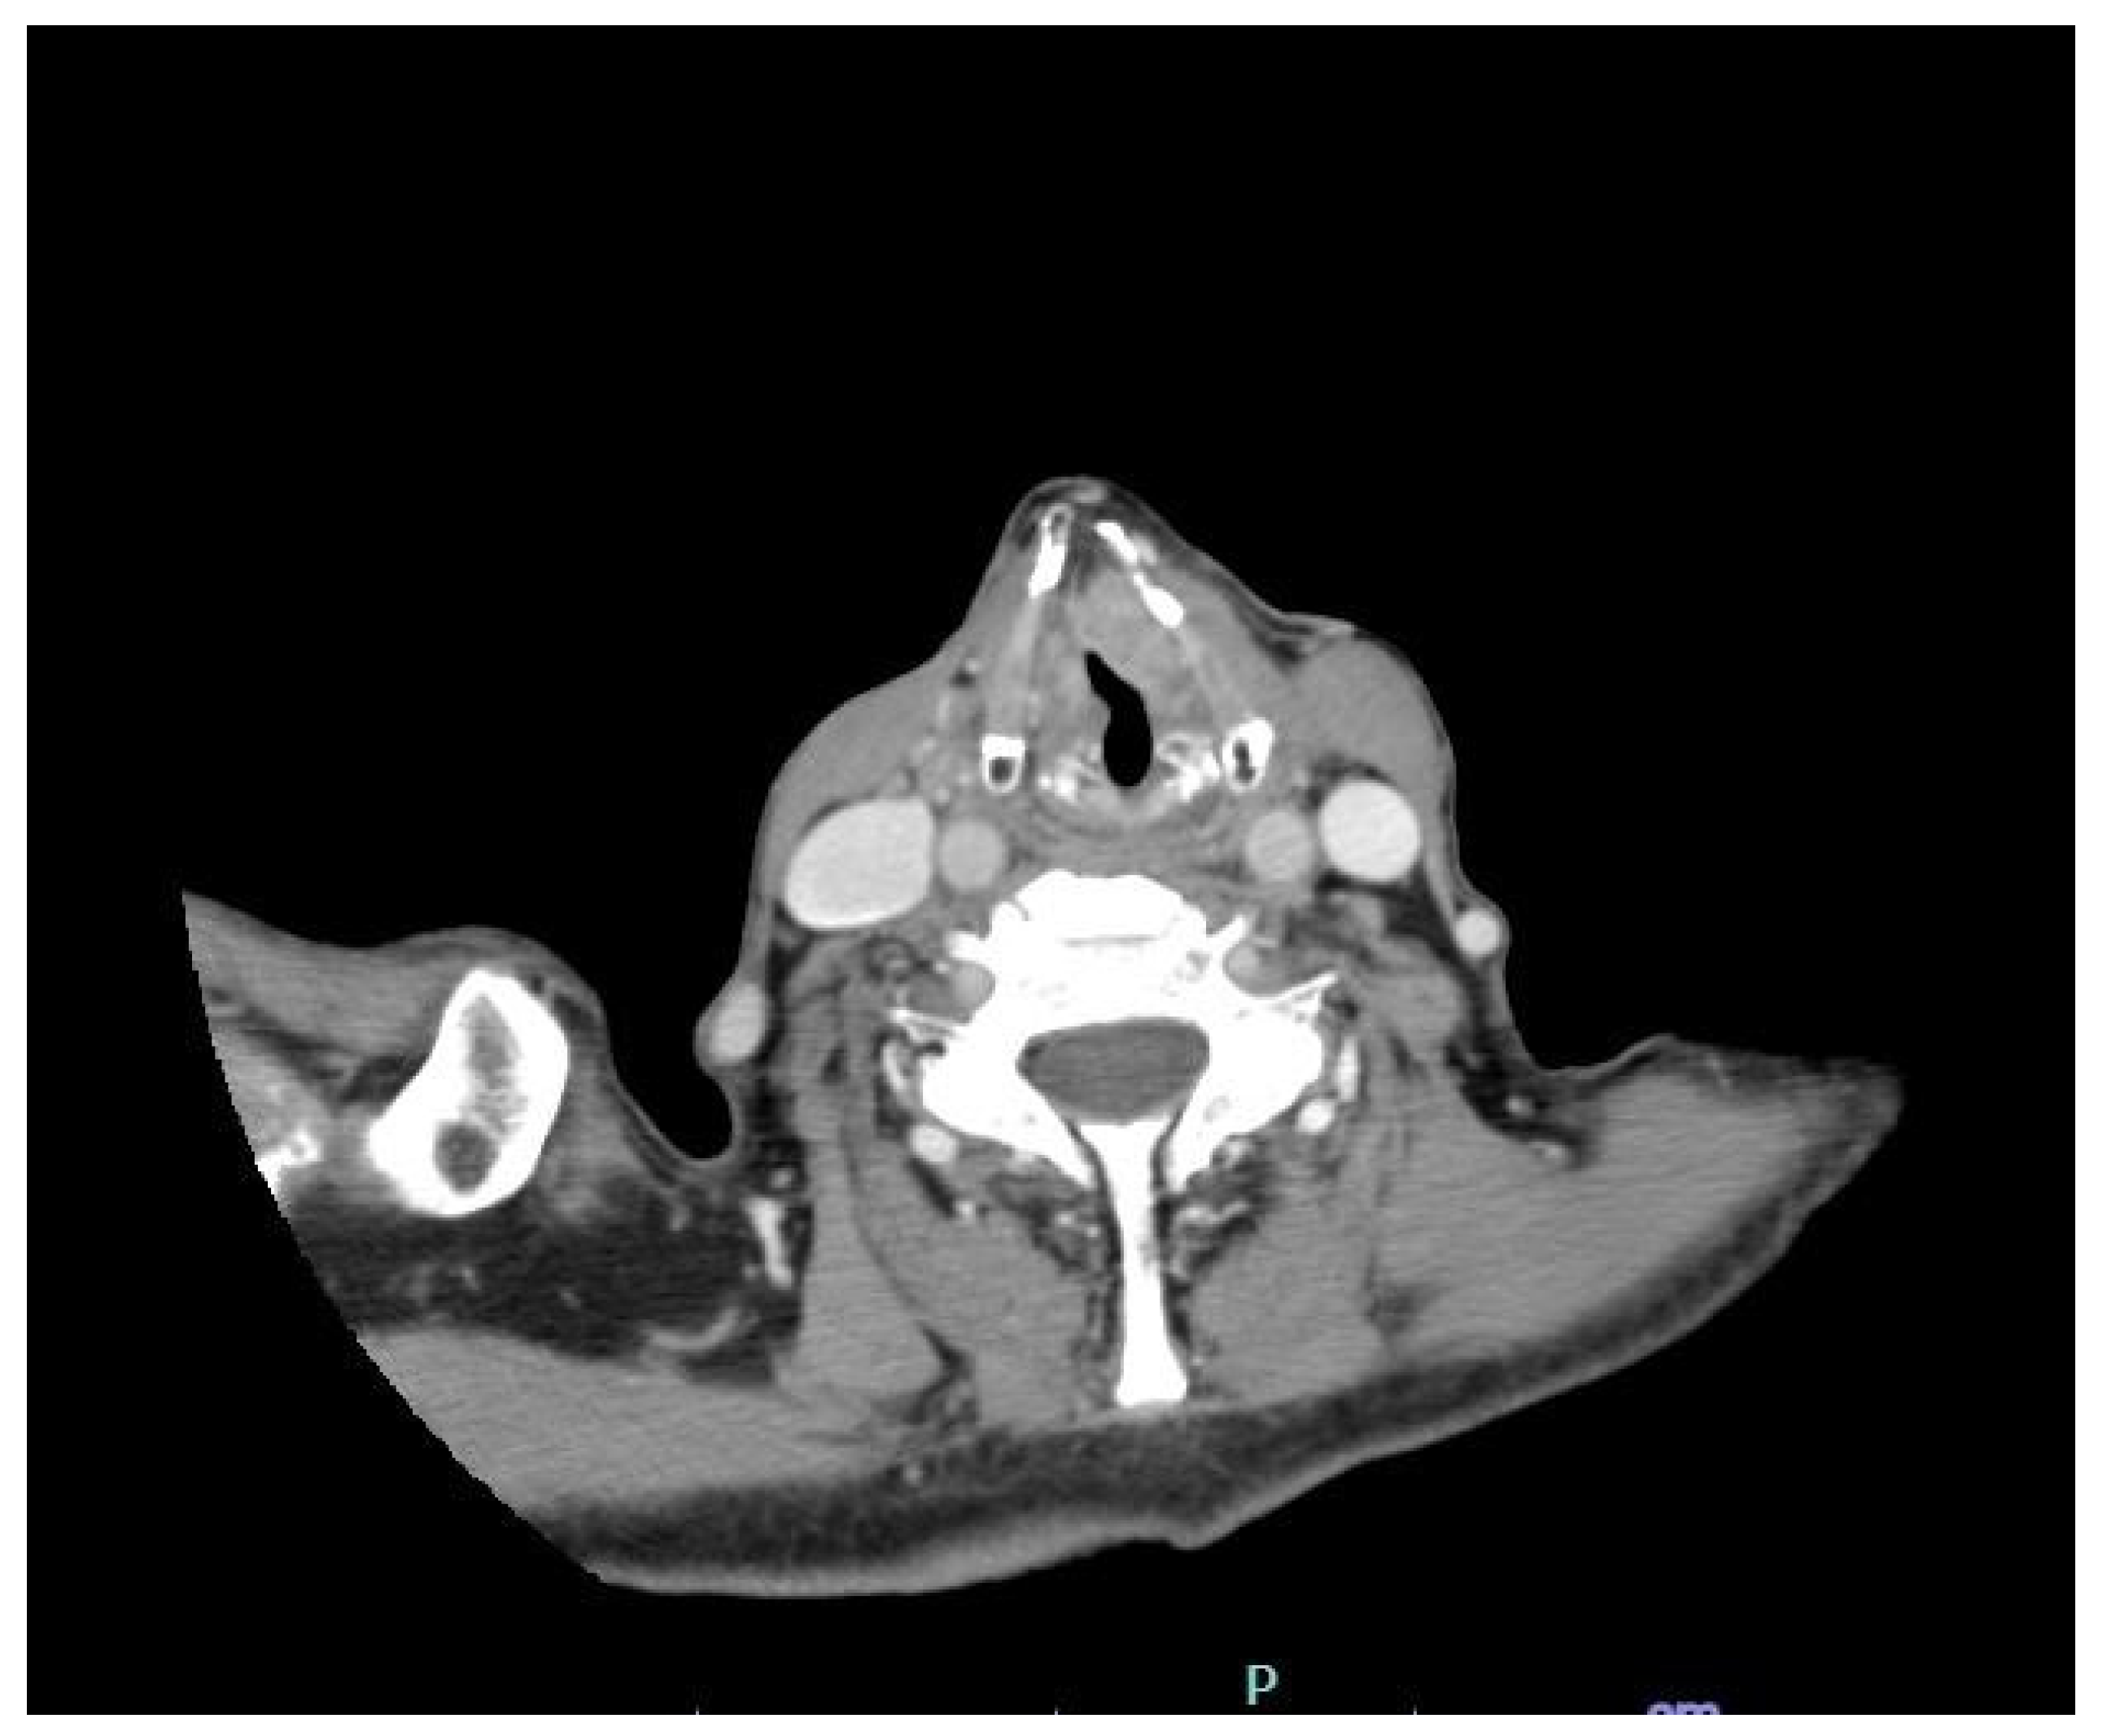

| 2 | Radiological investigation |